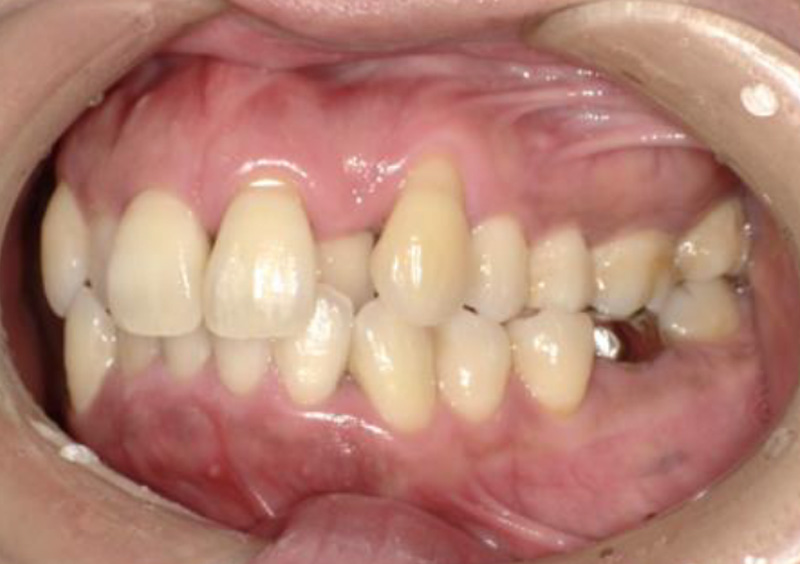

大人の矯正治療 歯ががたついている(叢生) 2025.10.22 【マルチブラケット矯正】前歯のがたつきが気になる 治療前 治療後 担当医 一瀬 悠依華 先生 主訴 前歯のがたつきが気になる 期間 1年 費用 39万円 治療内容 マルチブラケット装置(上下前歯部分矯正) 治療に伴うリスク 歯根吸収、歯肉退縮 関連症例